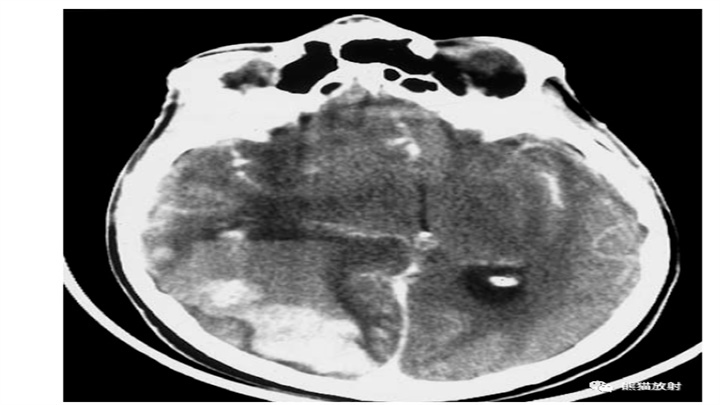

大量脑出血,累及左丘脑和基底节。明显的占位效应(中线结构向对侧明显移位)和脑室积血(同侧脑室变扁,右侧枕角积血)。然而,像往常一样,腹周水肿的数量仅限于周围边界。患者在数小时后死亡。